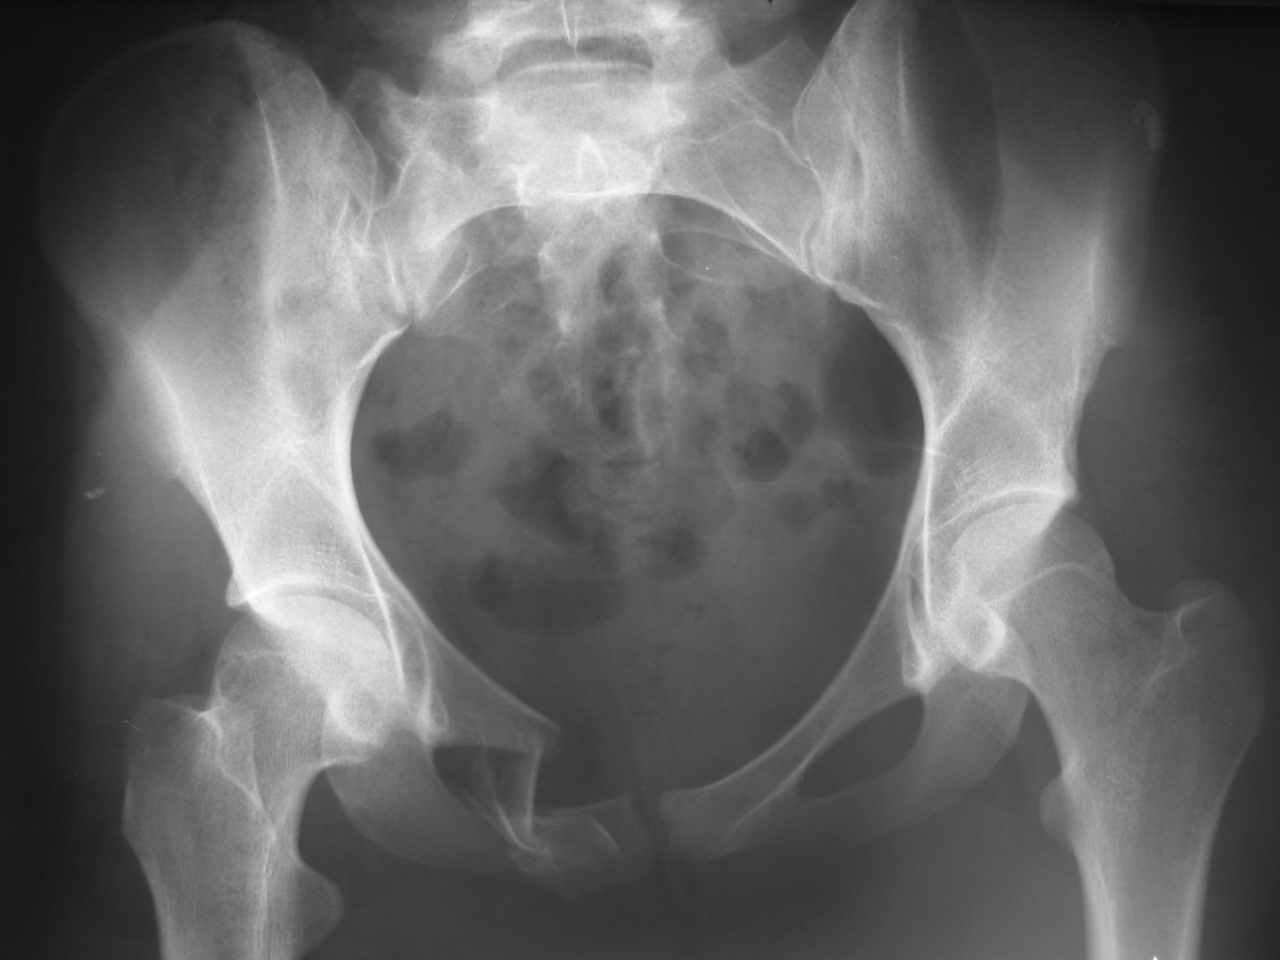

Уважаемые коллеги! К нам поступила молодая девушка 18 лет с оскольчатым переломом лонной и седалищной кости справа, после травмы прошел 1 месяц. Нужно ли вообще оперировать, стоит ли гнаться за анатомией? Или сделать комбинированный остеосинтез?